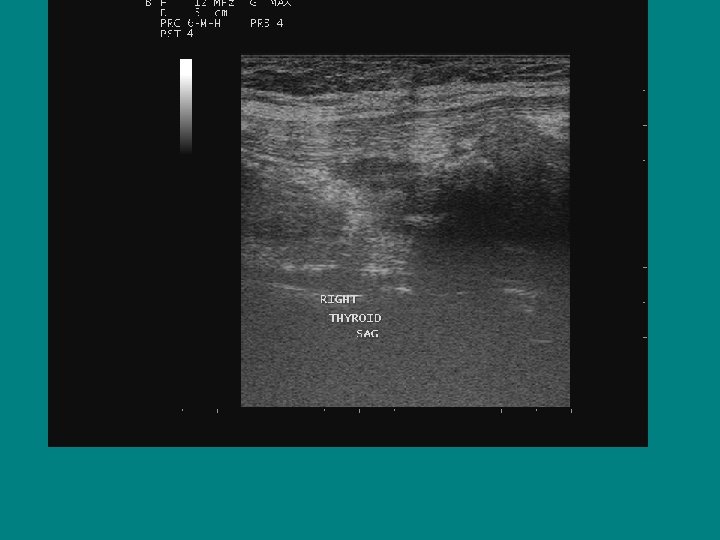

Right Left

Normal TSH with Irregular gland